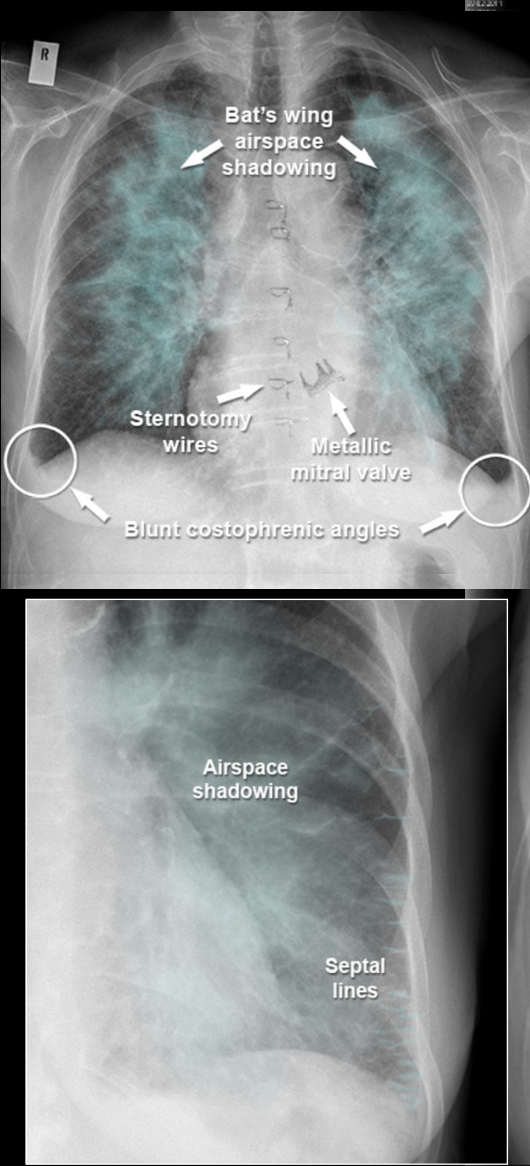

Lungestase/ødem:

Karakteristisk:

* Alveolært ødem

* Kerley B lines (septale linjer, horisontale, aldrig længere end 2 cm, ses bedst perifert i lungerne)

* Pleural effusion

* Kardiomegali

* Fremtrædende kar i overlapperne

Diagnose?

A

Hjertesvigt